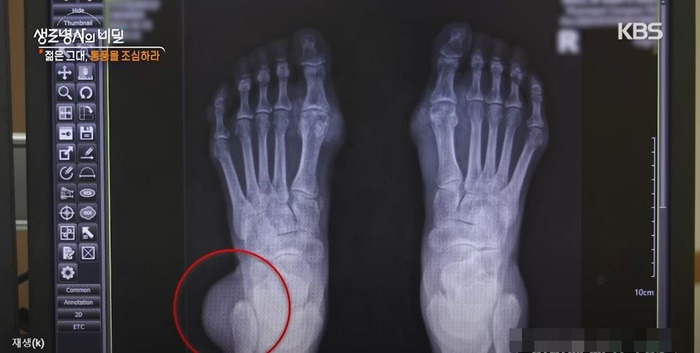

img_20241124212607_edac068c.jpg 통풍 환자의 엑스레이 / KBS1 '생로병사의 비밀'

통풍이 생기면 관절에 염증이 생겨 엄청난 통증이 따른다. 통풍이 심하면 급기야 관절이 변형되기까지 한다.

통풍에 걸리면 무증상 고요산혈증, 급성 통풍성 관절염, 간헐기 통풍, 만성 결절성 통풍이 나타난다.